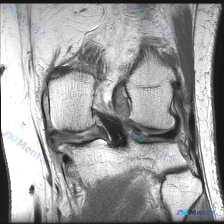

膝关节MRI读片:被"软骨异常"问题锚定后差点踩坑的病例

这是一张膝关节MRI矢状位T1加权像,图像质量良好,对比度清晰,无明显伪影,层面可显示股骨髁、胫骨平台、交叉韧带等核心结构。

- 核心异常发现:在胫骨平台前缘、前交叉韧带胫骨止点前方区域,可见一枚局灶性不规则低信号斑块影,信号强度和周围骨皮质、韧带类似,周围结构无明显信号紊乱。

这里发现一个关键矛盾:原问题说「软骨异常」,但这个异常病变是低信号,而正常软骨在T1加权像就是中等信号,原发软骨损伤也不会是均匀低信号,这说明这个病变本身就不是原发软骨组织,而是邻近结构的病变,可能是软骨损伤的来源,而不是软骨病变本身。

- 退行性骨赘/骨皮质重塑:最可能。位置在骨性边缘,信号和皮质一致,形态不规则,是这个位置最常见的情况,用这个病因解释最简单合理。

- 关节内骨软骨游离体:可能性次之。这个位置是游离体常见停留位置,信号也符合,关键需要多平面成像确认是否和母骨分离,如果是游离体可能引起关节交锁、急性软骨损伤,需要优先排查。